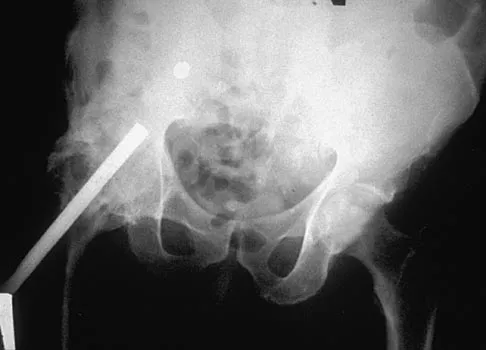

Question 8High Yield

Figure 2 shows the radiograph of a 72-year-old woman who reports pain after a fall. History includes several years of increasing thigh pain and limb shortening. Management consisting of an extensive work-up for infection reveals normal laboratory studies, a positive bone scan, and a negative hip aspiration. What is the most likely etiology of this complication?

General Orthopedics 2026 Practice Questions: Set 11 (Solved) - Figure 29

Explanation

The patient has a midstem periprosthetic fracture, which commonly results in loosening of the prosthesis. Patients who have a large amount of bone loss may require an allograft with the surgical reconstruction. Although the patient reported a fall, her history is also consistent with preexisting loosening of the prosthesis. Chronic infection has been shown in up to 16% of these fractures; however, the patient's work-up revealed no infection. Garbuz DS, Masri BA, Duncan CP: Periprosthetic fractures of the femur: Principles of prevention and management, in Cannon WD Jr (ed): Instructional Course Lectures 47. Rosemont, IL, American Academy of Orthopaedic Surgeons, 1998, pp 237-242. Bethea JS III, DeAndrade JR, Fleming LL, Lindenbaum SD, Welch RB: Proximal femoral fractures following total hip arthroplasty. Clin Orthop 1982;170:95-106.